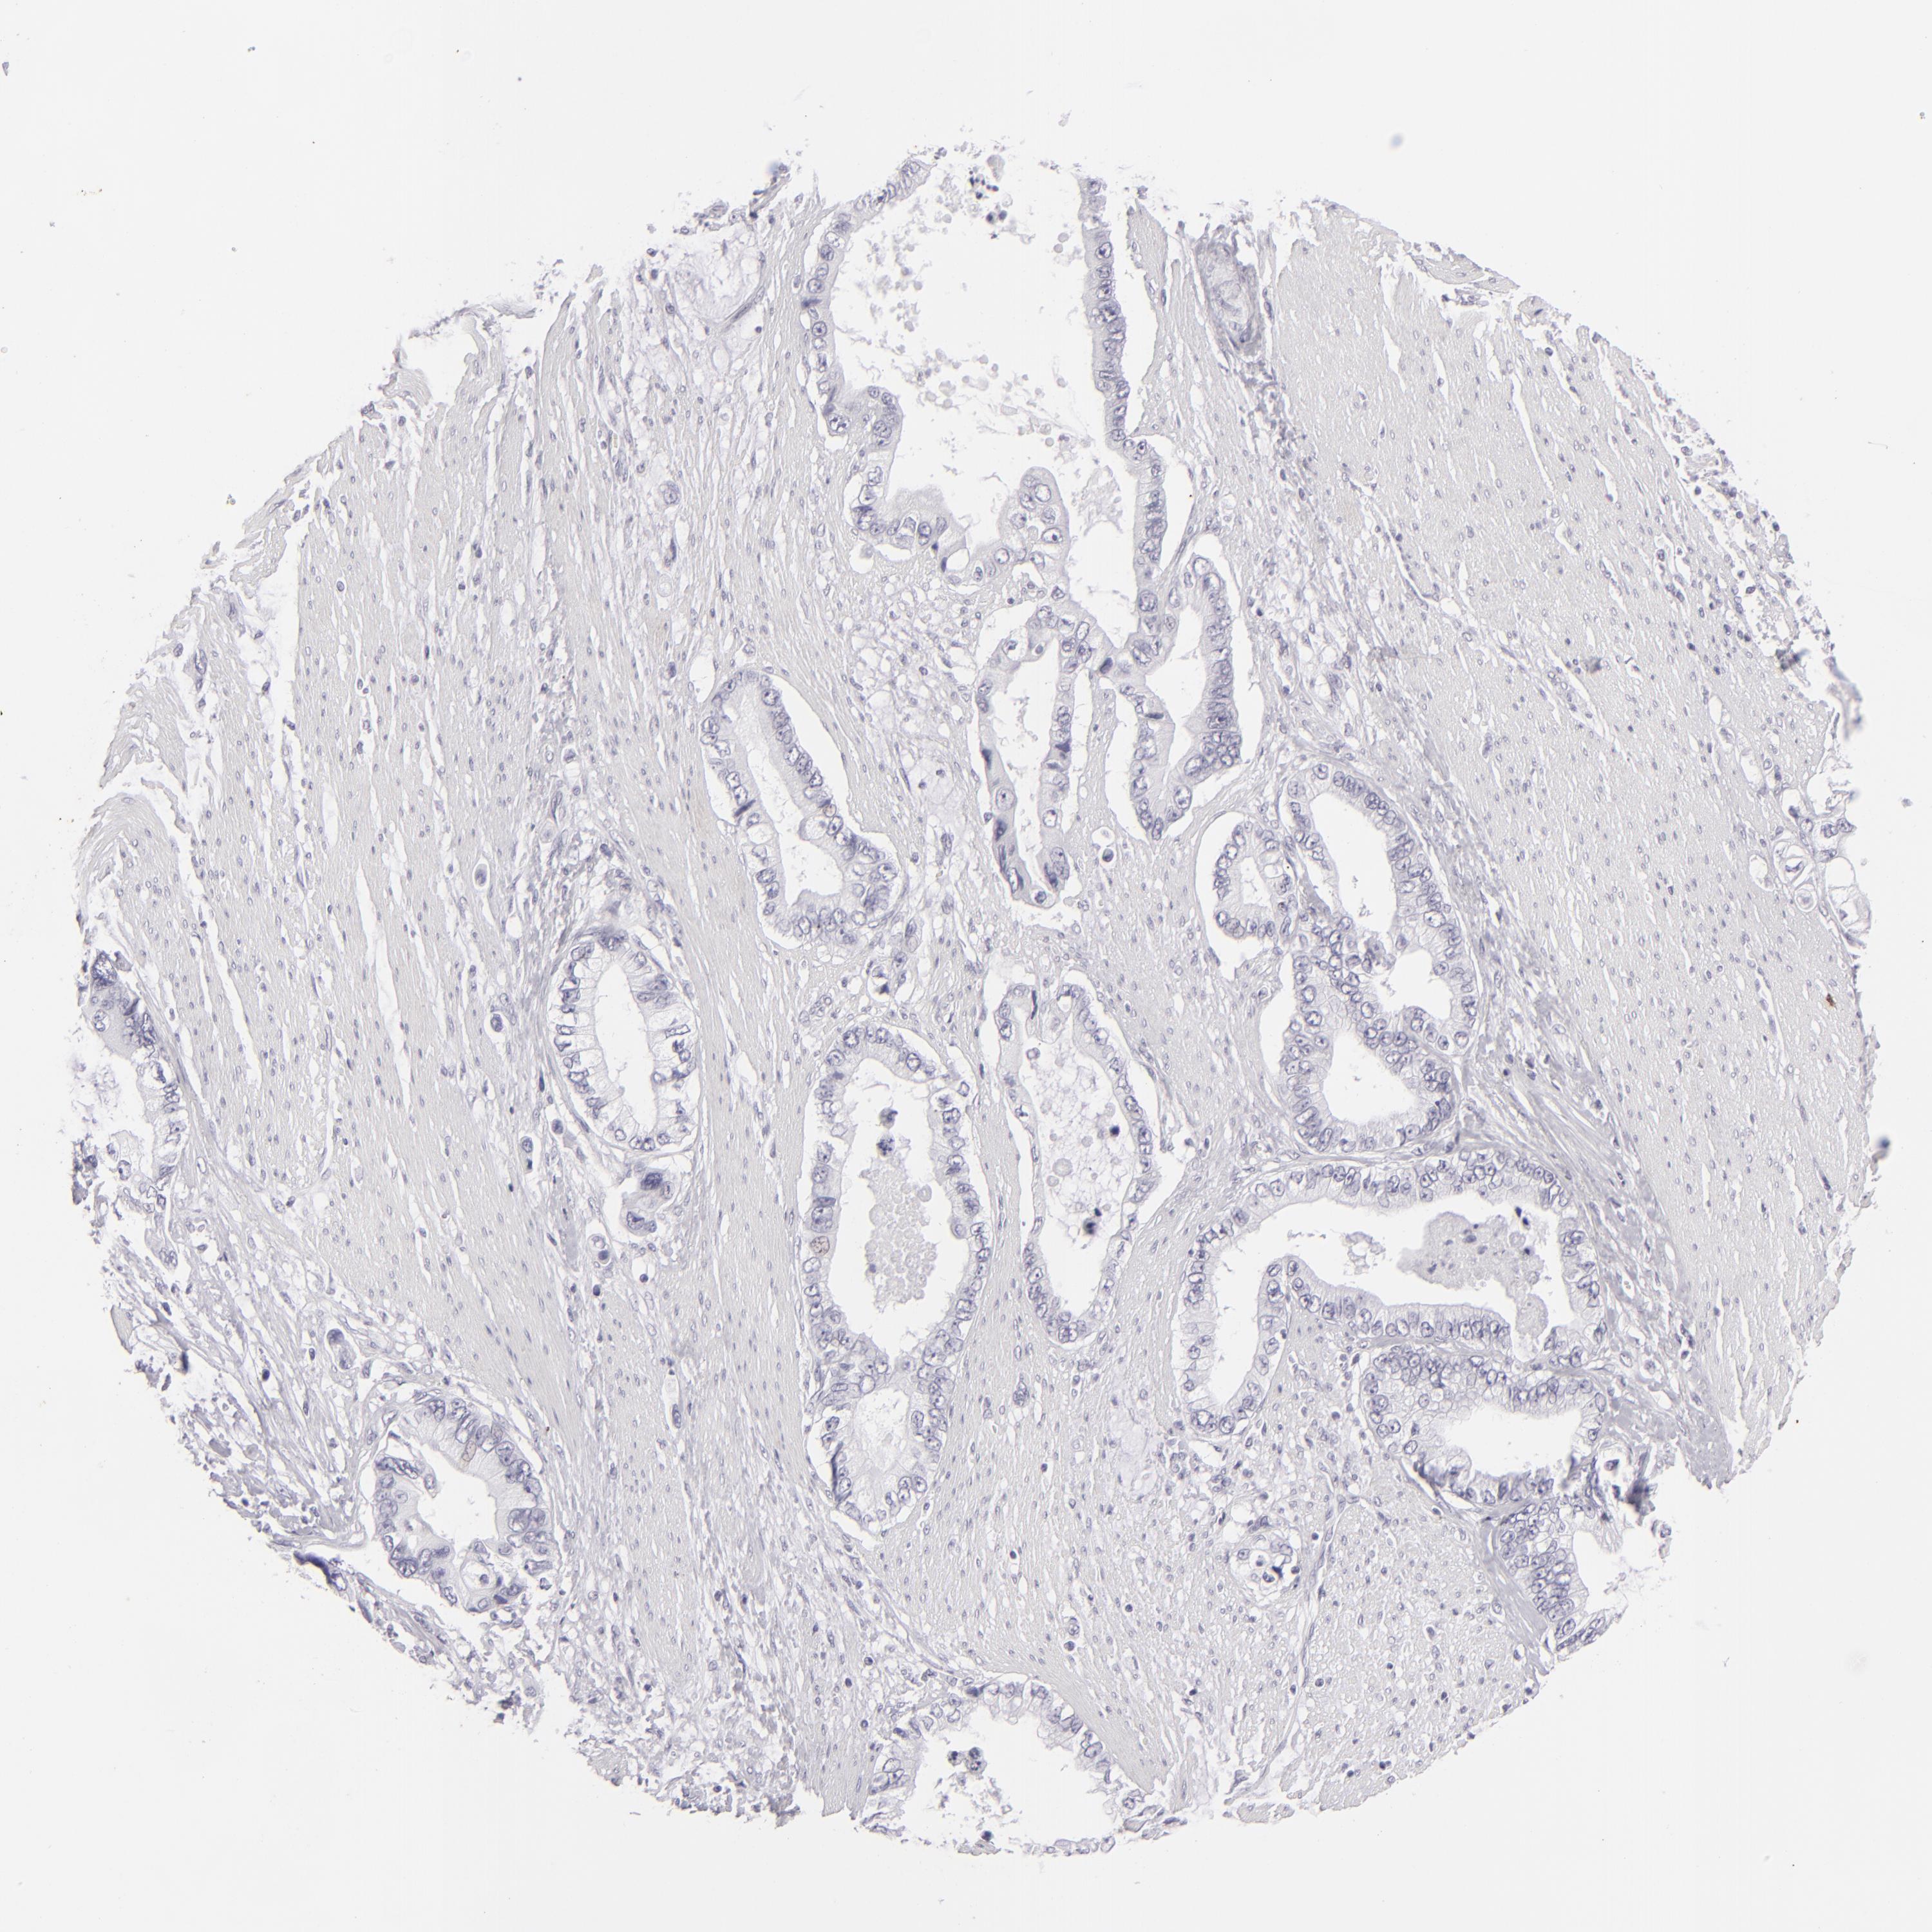

PANCREATIC CANCER - Protein expressioni

A mouse-over function shows sample information and annotation data. Click on an image to view it in a full screen mode. Samples can be filtered based on level of antibody staining by selecting one or several of the following categories: high, medium, low and not detected. The assay and annotation is described here.

Note that samples used for immunohistochemistry by the Human Protein Atlas do not correspond to samples in the TCGA dataset.

Antibody stainingi

Antibody staining in the annotated cell types in the current human tissue is reported as not detected, low, medium, or high, based on conventional immunohistochemistry profiling in selected tissues. This score is based on the combination of the staining intensity and fraction of stained cells.

Each image is clickable and will lead to virtual microscopy that enables deeper exploration of all samples and also displays staining intensity scores, fraction scores and subcellular localization as well as patient and tissue information for each sample.

Antibody HPA017917

Antibody HPA062908

Antibody CAB002153

Adenocarcinoma, NOS